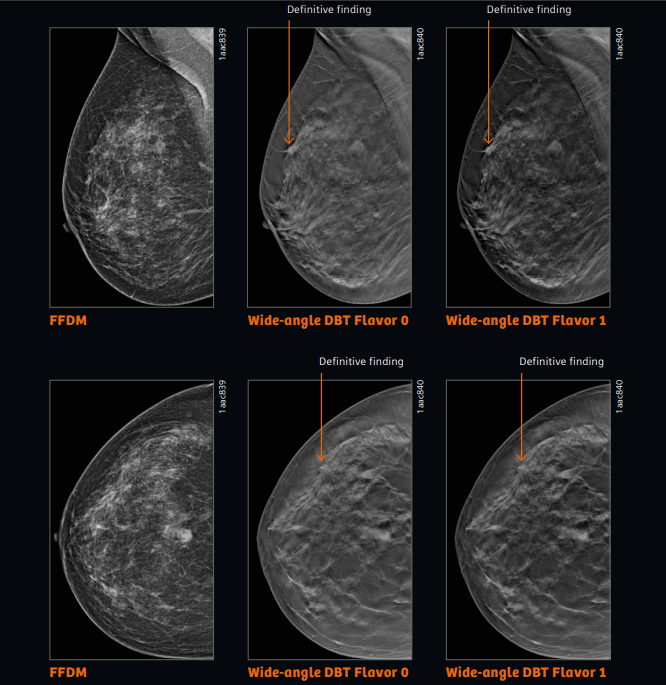

与目前的乳腺摄像仪器相比,MammoMat B.brilliant 通过进行同源性摄影,可以去除乳腺组织的重叠,清楚地描绘出病变。